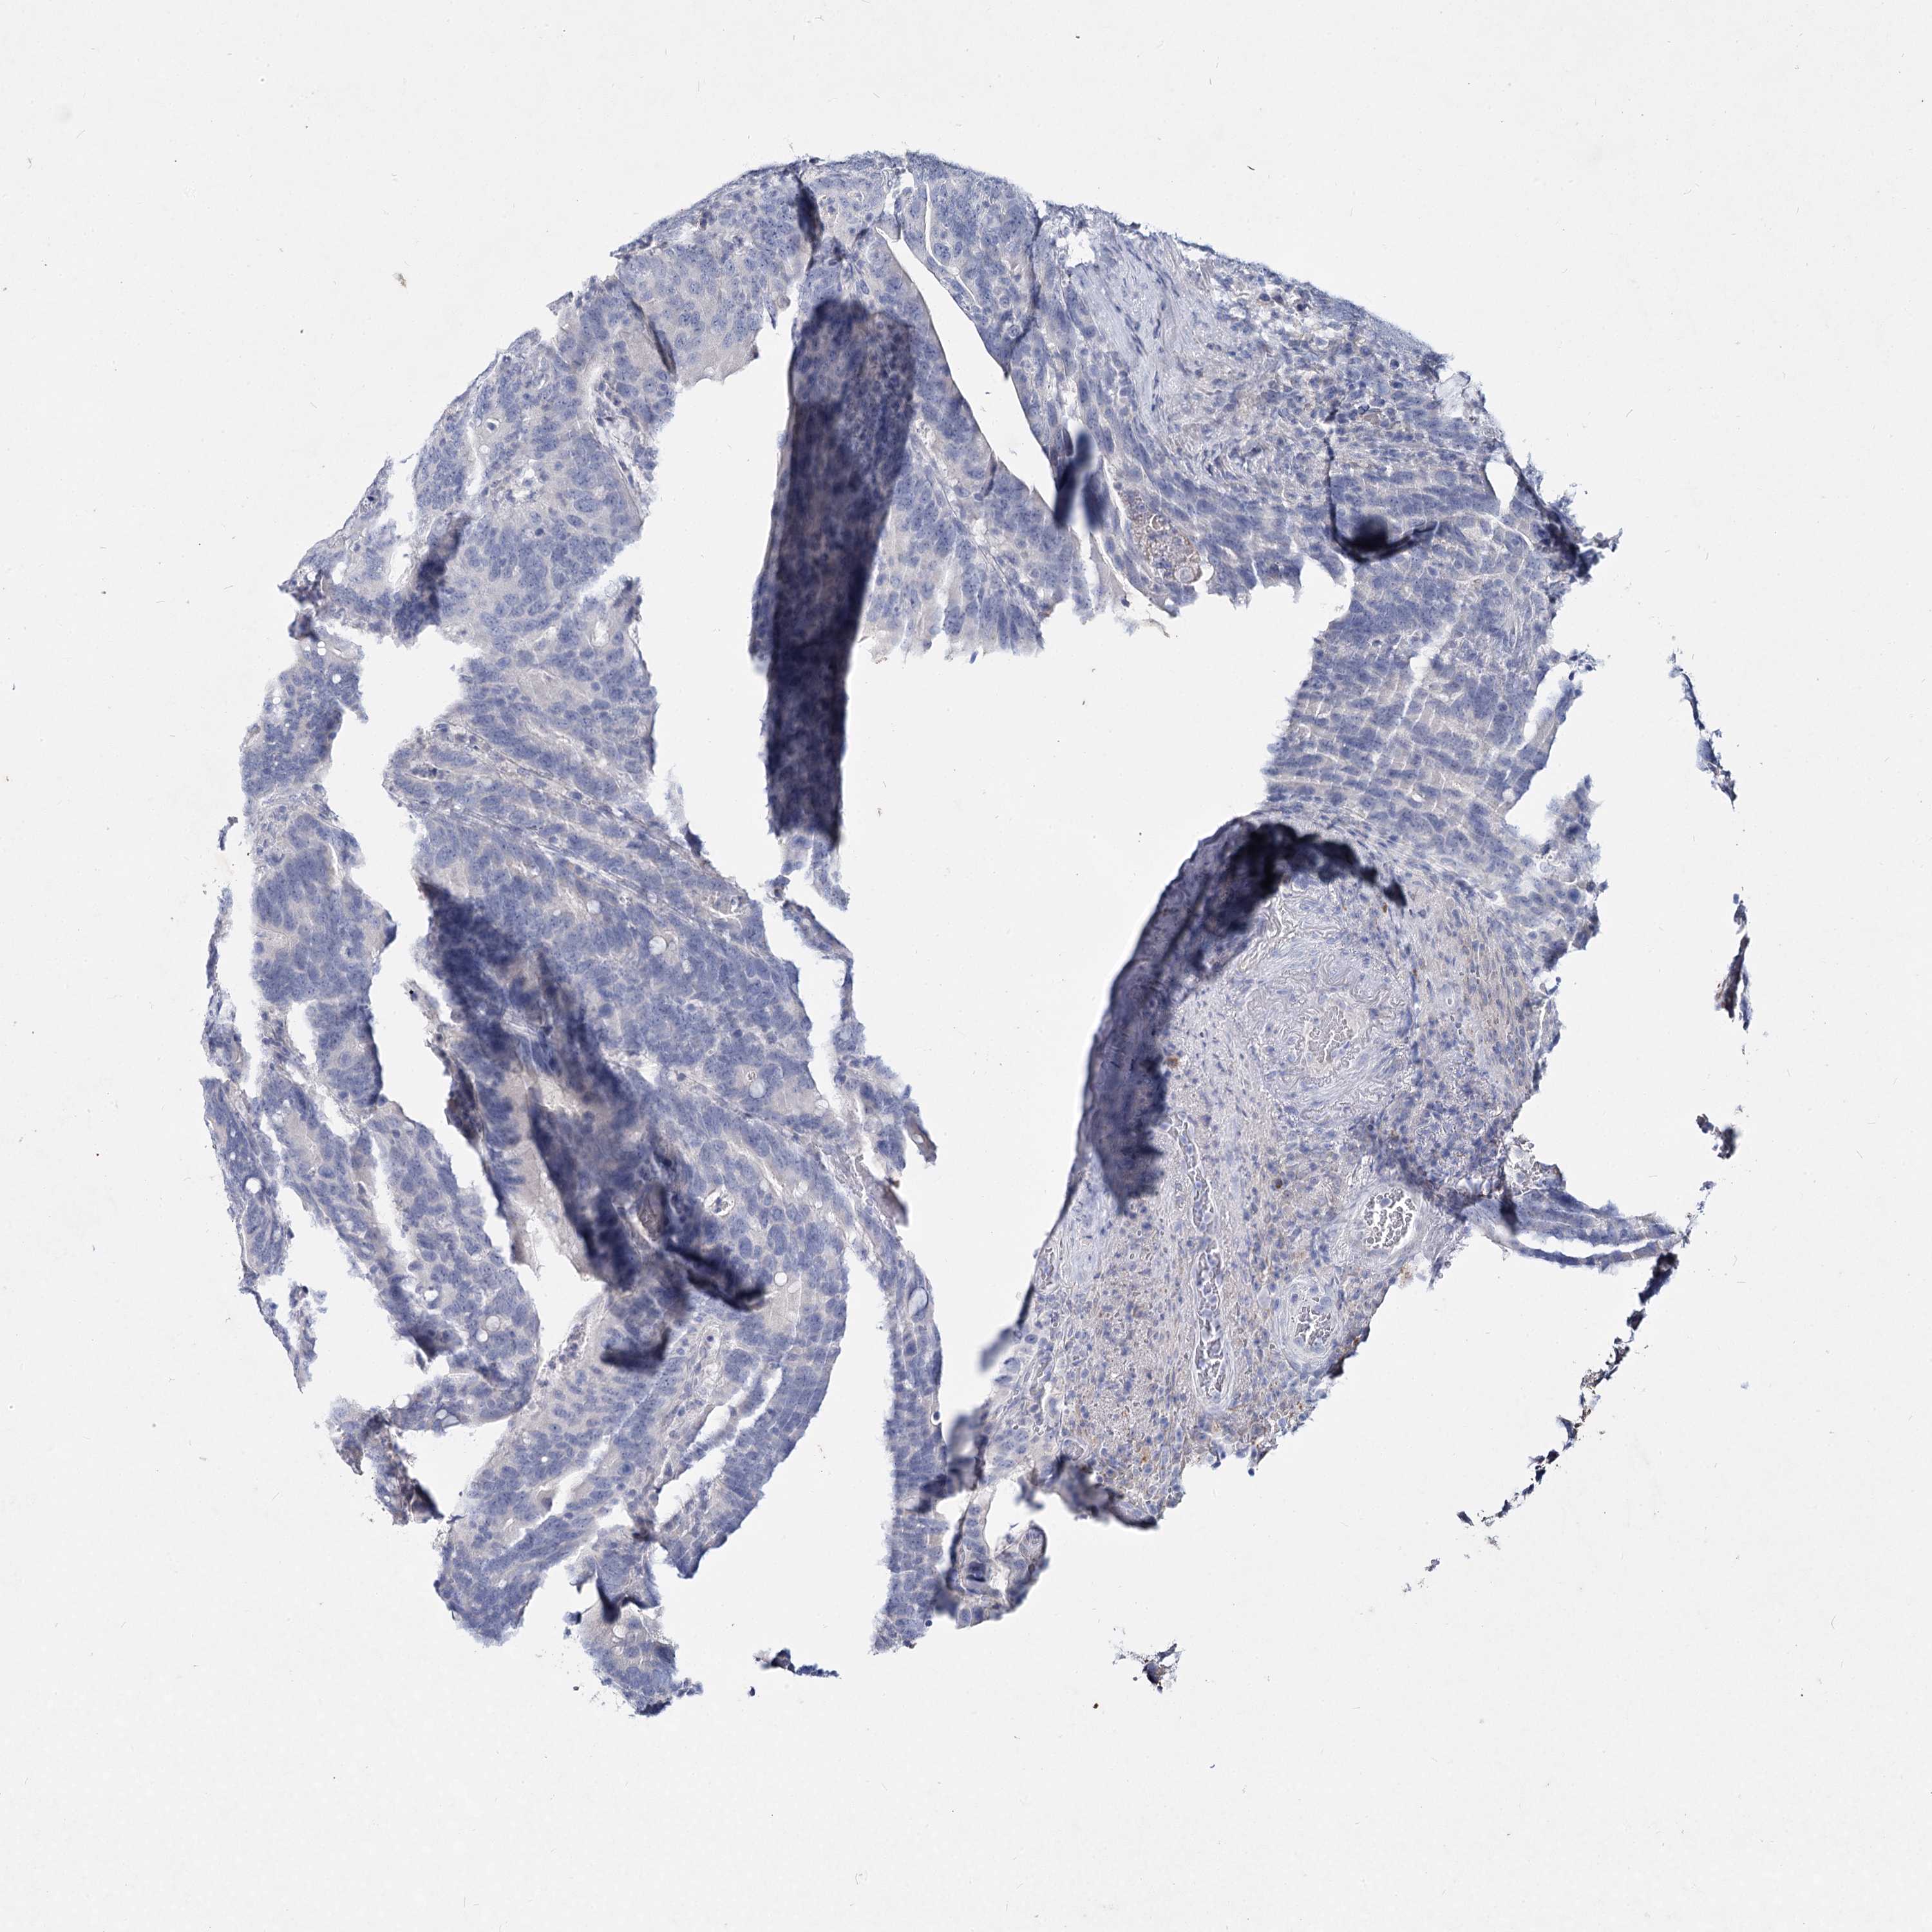

CANCER COLORECTAL CANCER Show tissue menu

Colorectal cancer

Human cancer

Colon adenocarcinoma